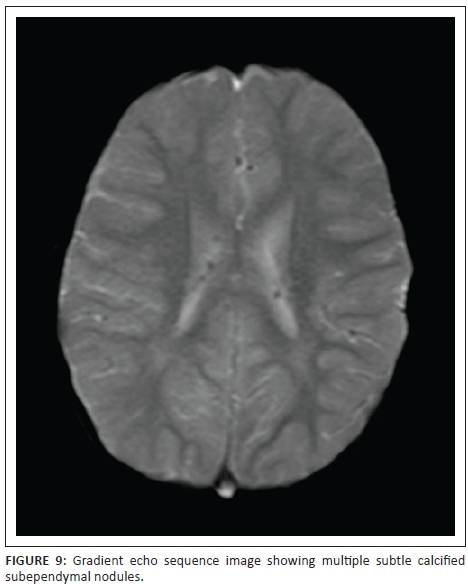

Subependymal nodules (SENS) are also hamartomatous in nature with a large proportion showing early calcification. These lesions are easily demonstrated on non-contrast CT scans or susceptibility-weighted imaging (SWI) or gradient echo sequences. See Figure 9, subtly showing the calcified SENS on a gradient echo sequence and Figure 10 demonstrating many more well-delineated calcified SENS in the patient reported here. Subependymal giant cell tumours or astrocytomas (SEGAS) are typically larger than SENS and occur particularly at the foramen of monro or the caudothalamic groove region. These are WHO Grade 1 tumours with slow progression, lack of local invasion, absence of surrounding oedema or cerebrospinal fluid (CSF) tumour seeding. mTOR pathway inhibitor Everolimus is an approved therapeutic agent for non-surgical management SEGAS.